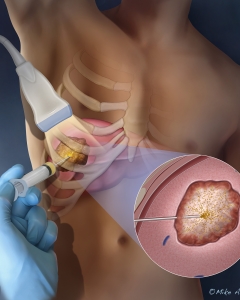

Welcome to my Patient and Professional Marketing page, where I harness the power of anatomical illustrations to educate and empower both patients and medical professionals. My unique approach combines artistry and education to convey complex surgical procedures and the utilization of medical devices in an easily understandable manner.